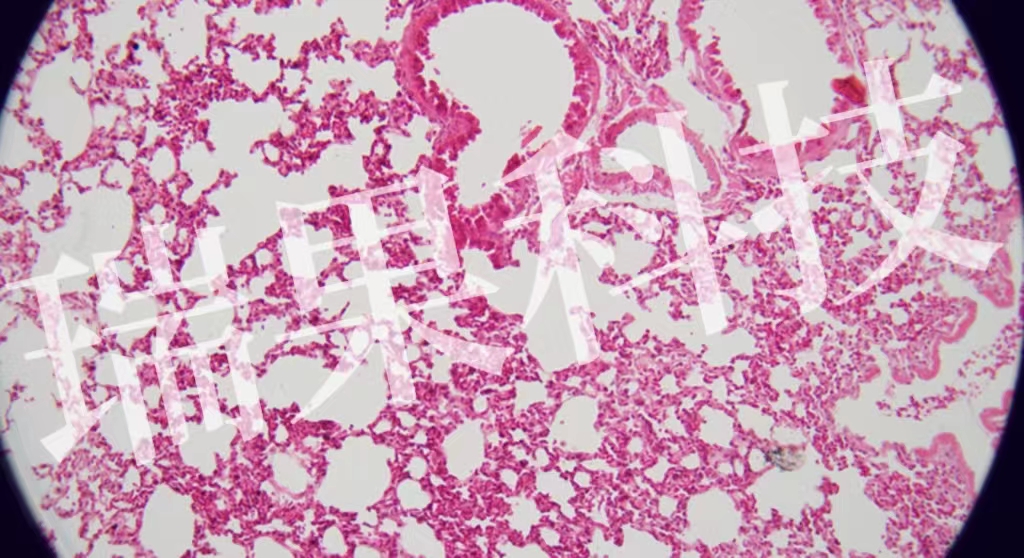

HE染色:苏木精 - 伊红染色法 ( hematoxylin-eosin staining ) ,简称HE染色法 ,石蜡切片技术里常用的染色法之一 。苏木精染液为碱性 ,主要使细胞核内的染色质与胞质内的核酸着紫蓝色 ;伊红为酸性染料 ,主要使细

HE染色:苏木精 - 伊红染色法 ( hematoxylin-eosin staining ) ,简称HE染色法 ,石蜡切片技术里常用的染色法之一 。苏木精染液为碱性 ,主要使细胞核内的染色质与胞质内的核酸着紫蓝色 ;伊红为酸性染料 ,主要使细胞质和细胞外基质中的成分着红色 。HE染色法是组织学、胚胎学、病理学教学与科研中最基本、使用最广泛的技术方法。

肺2-1-20x